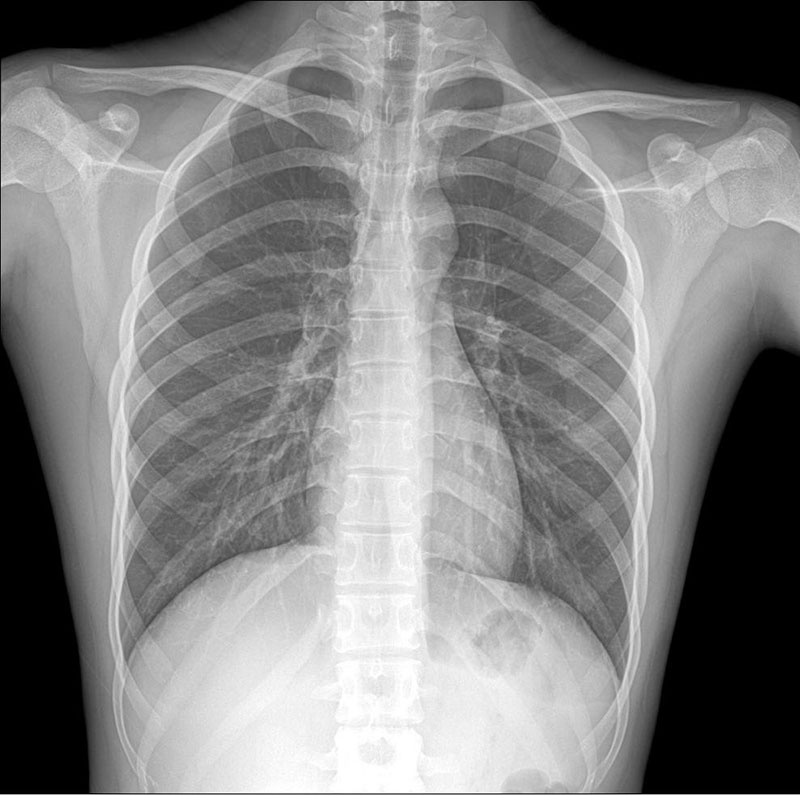

金旅7米體檢車醫療車,體檢信息管理系統:體檢車內配置有線局域網和4G無線網絡,可實現B超、心電圖、DR、純音電測聽等體檢結果數據自動匯總,打印報告;與站內互聯,信息傳回站內。所有設備和存放設備的柜均分別設有減震海綿,避免行車時震動對設備的損 傷。射線防護墻的轉角、連接處、進出門 等處的鉛板交叉重疊方式,確保射線不得直射、折射泄漏。通 過反吸收緩沖原理,抗震水平達5g,使車在行駛過程中加強避震、增大平穩度,有效保護了管球等主要部件安全。琴鍵式開關,選用起來比較可靠。紫外線消毒燈定時、有效殺毒。一個電源轉換開關,24V。